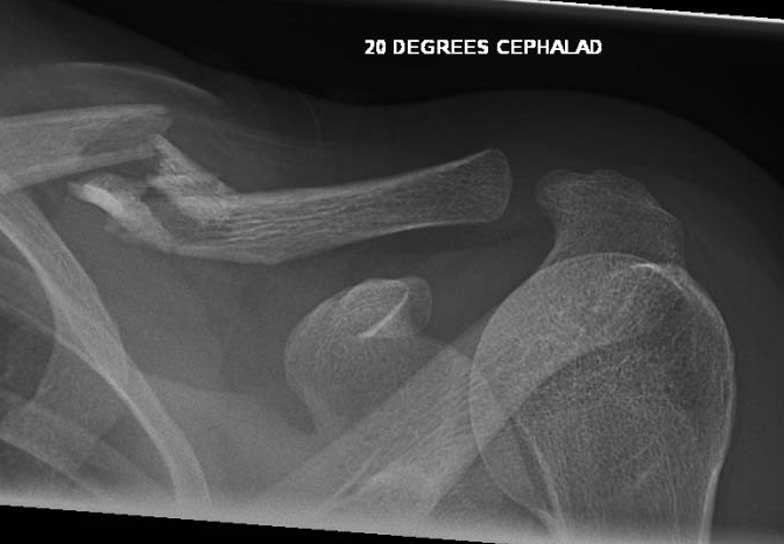

What do Distal Clavicle Fractures Look Like on X-ray and CT?

X-RAY

Click an image to enlarge